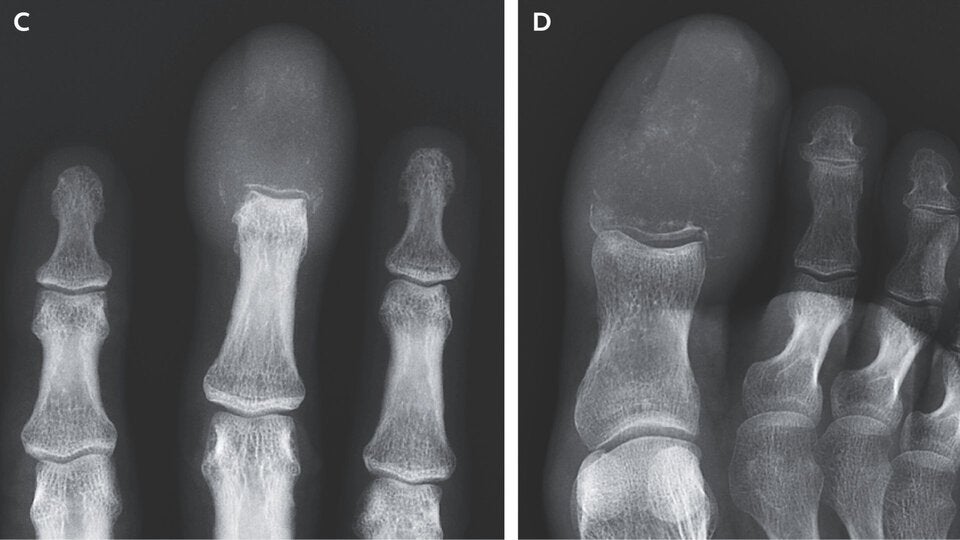

Viele vertrauen auf die Goldfaden-Akupunktur, auch in den Füßen diverser Patienten fand man Goldfäden nach der Behandlung.

© Live Science